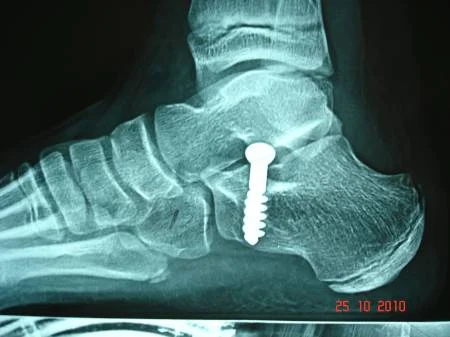

El tratamiento quirúrgico en recurso para corregir el pie plano, cuando ha fallado el tratamiento conservador. Existen muchas técnicas quirúrgicas, pero quizás la que está más difundida es la descrita por el Dr. Recaredo Álvarez en 1972, la técnica de Calcáneo Stop, la cual reconstruye la relación entre los huesos astrágalo calcáneo, sin actuar en superficies articulares, actuando en el seno del tarso constituyendo el concepto llamado artrorrisis, realizada con un tornillo especial de bloqueo.

La técnica de calcáneo stop es un procedimiento quirúrgico sencillo y ambulatorio, el cual permite corregir el pie plano valgo juvenil (8 a 12 años de edad), con excelente resultados. El paciente inicia el apoyo a las 24 horas, tendiendo a caminar metiendo los pies, lo cual es normal en las primeras semanas del postoperatorio, lo padres no deben preocuparse por este hecho.

Caso clínico: Paciente de 10 años de edad, quien presentaba pie plano valgo doloroso, con acortamiento del tendón de Aquiles (gemelos). Fue intervenido quirúrgicamente practicándose  cura operatoria según la técnica de calcáneo stop, con la colocación de tornillo de bloqueo en el seno del tarso y alargamiento del tendón de Aquiles según técnica de Vulpius. Excelente resultado postoperatorio. Ver imágeness arriba y a la derecha.